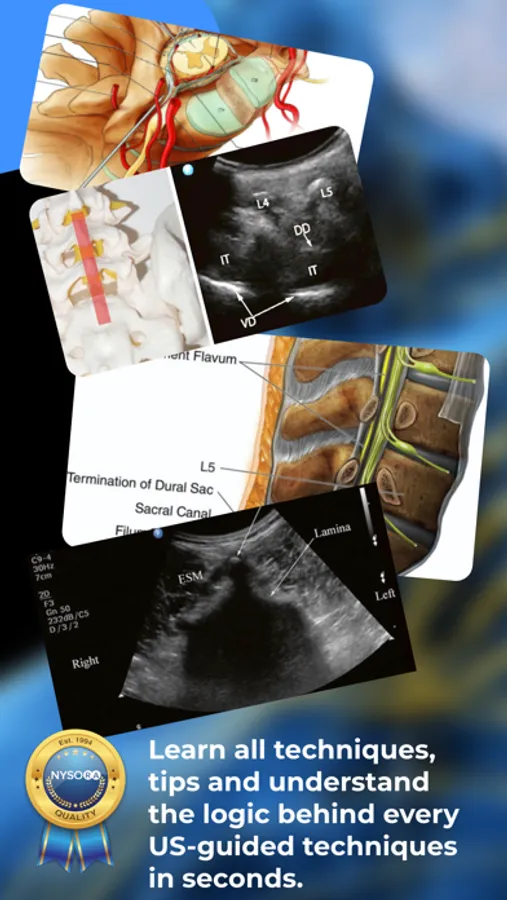

Published by the world’s leading authority on Ultrasound-Guided Interventional Pain procedures. Details the most practical and applicable techniques in pain medicine. Clear images, illustrations, ultrasound images, reverse ultrasound anatomy illustrations and animations. Features both ultrasound-guided pain and MSK procedures.

Loaded with practical clinical tips. Regularly enhanced by NYSORA’s illustrations and animations;

Tips on how to get the best images and results with injections.